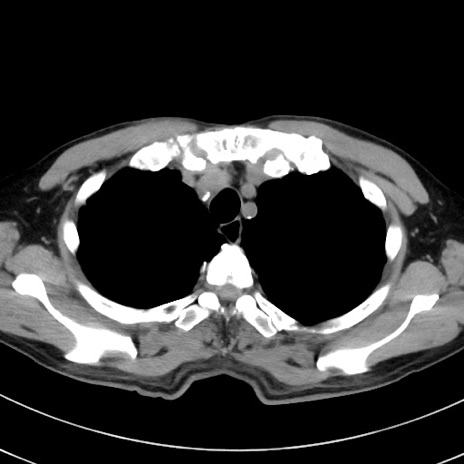

症例38(横断像)

【症例】70歳代 男性

【主訴】腹痛・嘔吐

【現病歴】昨晩より、嘔吐・腹痛あり。今朝になっても嘔吐あり。来院。

【既往歴】心臓バイパス手術、開腹胆摘、腸閉塞

【身体所見】BP 107/71mmHg、HR 116/min、腹部:平坦、軟、下腹部に軽度圧痛あり。反跳痛なし。

【データ】WBC 15100、CRP 0.32